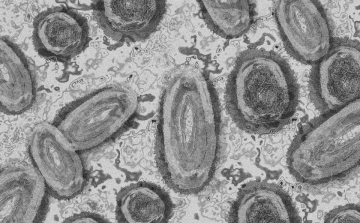

Tovább nőtt a majomhimlő-fertőzöttek száma Magyarországon

Újabb két embernél igazolt majomhimlő-fertőzést a Nemzeti Népegészségügyi Központ (NNK) a 33. héten - augusztus 15-től 21-ig -, ezzel 64-re nőtt a magyarországi esetek száma.

Meghaladta a 13 ezret a majomhimlő-fertőzöttek száma az Egyesült Államokban

Meghaladta a 13 ezret a majomhimlő-fertőzöttek száma az Egyesült Államokban, a legtöbb esetet Kaliforniában és New York államban regisztrálták.

Megfertőződött a majomhimlővel egy gyerek Németországban

Megfertőződött majomhimlővel egy négyéves kislány Németországban - jelentették kedden német hírportálok az országos közegészségügyi intézet (RKI) adatai alapján.

Tovább nőtt a majomhimlő-fertőzöttek száma Magyarországon

Újabb kilenc, 23-50 éves férfinél igazolták a majomhimlő-fertőzést Magyarországon, ezzel 42-re nőtt a fertőzöttek száma - közölte a Nemzeti Népegészségügyi Központ (NNK) csütörtökön az MTI-vel.

Tovább nőtt a majomhimlő magyar fertőzöttjeinek száma

Újabb hat embernél diagnosztizálták a majomhimlő vírusát, így harmincra emelkedett az igazolt fertőzöttek száma Magyarországon - közölte a Nemzeti Népegészségügyi Központ (NNK) pénteken az MTI-vel.